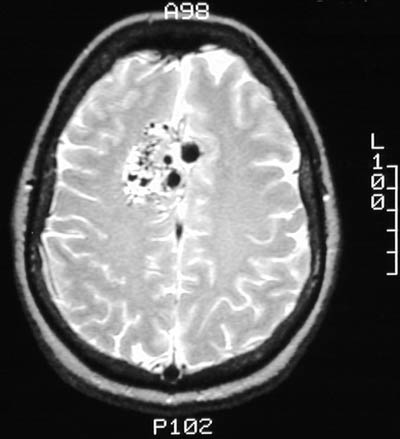

There is a vascular malformation in the right medial frontal lobe, as seen above in sagittal view with T1 weighted MRI scan. The lesion is seen below in axial view with T1 and T2 weighted MRI scans. Note the large, irregular vascular channels.